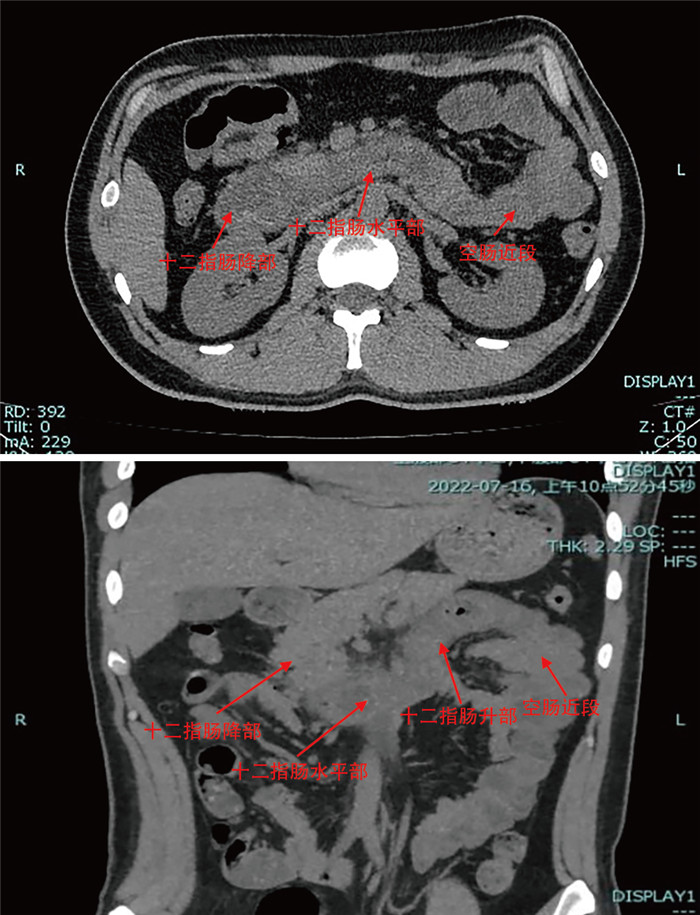

Construction and verification of prediction model and treatment strategy for shunt loss after portal hypertension TIPS

QIAN Jinyu, YANG Peipei, ZHANG Yang, XIE Bo, WU Di, TANG Xiaoyun, ZHANG Leiming, TAN Yulin, ZHANG Zichen

2025, 23(7): 1107-1110. doi: 10.16766/j.cnki.issn.1674-4152.004075

429 3

Abstract:

Objective   To identify the risk factors of shunt dysfunction after transjugular intrahepatic portosystemic shunt (TIPS) in patients with portal hypertension, to construct and verify the clinical prediction model, and to formulate corresponding countermeasures for different types of shunt dysfunction, so as to provide reasonable treatment for patients.   Methods   The clinical data of 120 patients who underwent TIPS in the interventional department of the First Affiliated Hospital of Bengbu Medical University from January 2020 to December 2024 were retrospectively analyzed. Subsequent to the surgical procedure, the subjects were categorized into two distinct groups, namely the shunt dysfunction group and the non-dysfunction group, with the respective numbers amounting to 35 and 85 cases. Variables with significant differences were included in multivariate logistic regression analysis to determine the independent risk factors, and a prediction model was constructed based on this. The discrimination capacity of the model was evaluated by means of the ROC curve. Finally, the corresponding countermeasures are proposed for the various types of shunt failure.   Results   Multivariate logistic regression analysis demonstrated that anticoagulation therapy (OR=15.754, P=0.030), portal vein thrombosis (OR=0.052, P=0.008) and portal vein puncture site (OR=0.064, P=0.007) were independent influencing factors for shunt dysfunction after TIPS. The area under the ROC curve (95% CI) of the constructed model was 0.933 (0.882-0.983), and the corresponding optimal cut-off value was 0.866. The sensitivity was 0.894, and the specificity was 0.971.   Conclusion   Therapy, portal vein thrombosis and portal vein puncture site are independent influencing factors of shunt dysfunction after TIPS. The prediction model constructed accordingly has the potential to assist clinicians in the early identification of risks and the implementation of intervention measures.